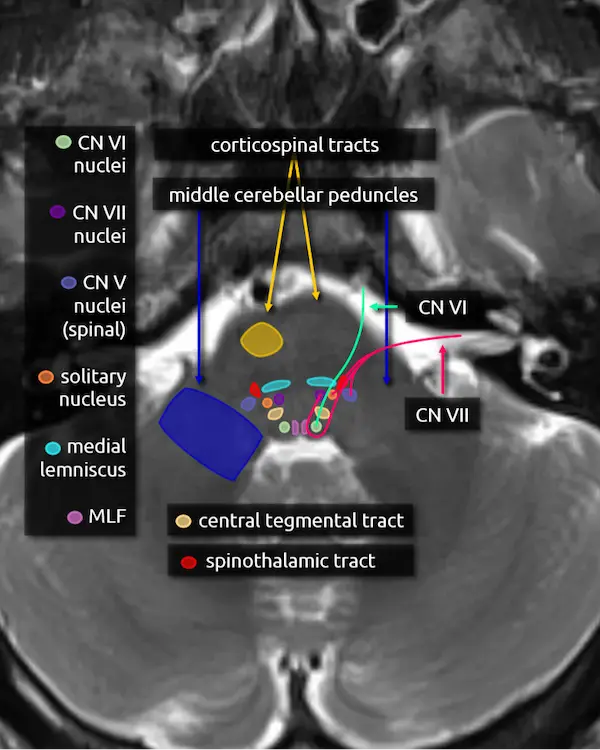

1. Corticospinal tracts

2. Middle cerebellar peduncles

3. Medial lemniscus

4. Medial longitudinal fasciculus (MLF)

5. Abducens nucleus (CN VI)

The abducens nucleus is located in the dorsal pons at the level of the internal auditory canals. The facial colliculi are the two bumps along the dorsal surface of the pons at this level, which are formed by the facial nerve coursing over the abducens nucleus.

Absence of the abducens nucleus occurs in horizontal gaze palsy with progressive scoliosis (HGPPS), which results in an abnormal contour of the posterior pons due to flattening of the facial colliculi.

6. Abducens nerve (CN VI)

The abducens nerve courses anteriorly from the abducens nucleus and exits the ventral pons at the pontomedullary junction. After traversing the prepontine cistern, the nerve enters Dorello's canal, where it is relatively fixed in place. It also has the longest subarachnoid course of the cranial nerves. These two features make it particularly susceptible to stretching-related injury, e.g., in the setting of brain herniation. After Dorello's canal, the nerve enters the cavernous sinus, where it is susceptible to mass effect from space occupying lesions, e.g., a mass or a cavernous internal carotid artery aneurysm.

The abducens nerve innervates the ipsilateral lateral rectus muscle, responsible for eye abduction. Damage will cause horizontal diplopia.

7. Facial nucleus (CN VII)

The facial nucleus is located in dorsal pons anterior to the abducens nucleus and posterior to the medial lemniscus.

8. Solitary nucleus

The solitary nucleus is located lateral to the facial nucleus in the lower pons and extends to the upper medulla. It contributes to the facial, glossopharyngeal, and vagus nerves.

Damage to the solitary nucleus may manifest as decreased taste sensation on the ipsilateral tongue.

9. Spinal nucleus of the trigeminal nerve (CN V)

The spinal nucleus of the trigeminal nerve is the inferior continuation of the main sensory nucleus of the trigeminal nerve (see level 3). It is involved in sensation of the head and face. It receives afferent fibers from the facial, glossopharyngeal, and vagus nerves.

10. Facial nerve (CN VII)

The facial nerve courses posteriorly from the facial nucleus before looping over the ipsilateral abducens nucleus and exiting the anterolateral pons at the pontomedullary junction. It then enters the internal auditory canal with the vestibulocochlear nerve (CN VIII). Four nuclei contribute to the facial nerve; the three listed above, and a fourth called the superior salivary nucleus responsible for parasympathetic fibers located medial to the facial nucleus, not pictured here. The nerve has motor, sensory, and parasympathetic functions:

11. Spinothalamic tract

12. Central tegmental tract

Predicting deficits of a pontine lesion

You now know enough pontine anatomy to predict the most likely symptoms for a lesion anywhere in the majority of the pons. See the figure on the right for a simplified but practical way of conceptualizing this anatomy.

Lesions in the anterior aspect of the pons are likely to damage the corticospinal and corticobulbar tracts, producing weakness or paralysis. Lesions in the center of the pons are likely to damage the transverse pontine fibers, causing ataxia. Remember that the corticopontocerebellar pathway makes up a large part of those fibers. Lesions towards the back of the pons are likely to involve the medial lemniscus and spinothalamic tract, producing sensory deficits. Lesions that involve the most posterior aspect of the pons surrounding the fourth ventricle are likely to cause diplopia due to damage to the MLF and/or the abducens nerve (CN VI), depending on the level.